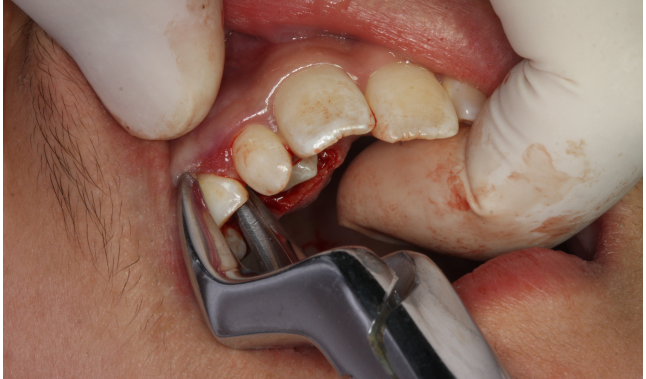

圖10.拔除右側(cè)乳尖牙

圖11.從乳尖牙到13牙冠區(qū)域去皮質(zhì)骨化處理